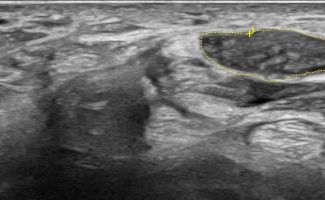

Hand Ultrasound examines joints, tendons, ligaments, nerves, and soft tissues of the hand. Pathologies that can be diagnosed by Hand Ultrasound are numerous, including:

Soft Tissue Pathologies

- Ganglia

- Tumors